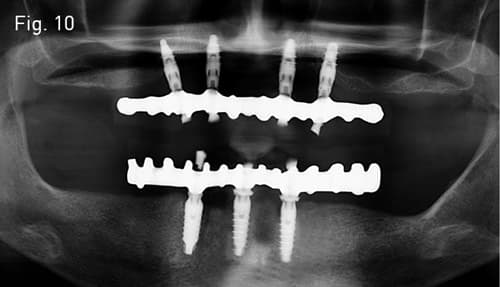

İmplant üstü vidalı hibrit protez çözümü.